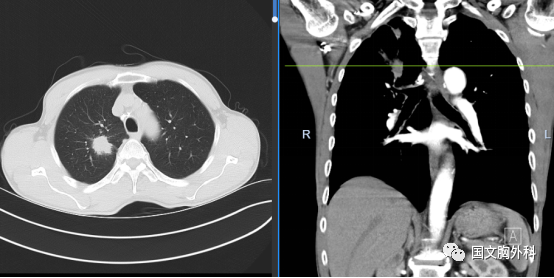

周大爺,發(fā)現(xiàn)肺占位1個月。CT下觀察右肺上葉腫物延續(xù)至肺門,穿刺病理提示:肺鱗癌。有手術(shù)機會,家屬同意手術(shù)治療。